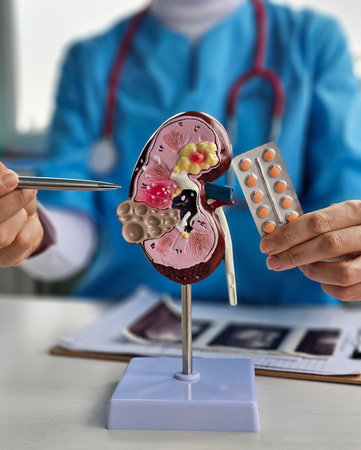

Kidney disease, Chronic kidney disease ckd, Doctor hold human model to treat and study in hospital.

Chronic kidney disease, doctor with model for treatment urinary system, urology, Estimated glomerular filtration rate eGFR.

Doctor examines renal model while holding a medication strip in a clinical setting for educational purposes

Kidney disease, Chronic kidney disease ckd, Doctor hold human model to treat and study in hospital.

Kidney disease, Chronic kidney disease ckd, Doctor hold human model.

Human Kidney Model with Chronic Kidney Disease Damage Held by Doctor